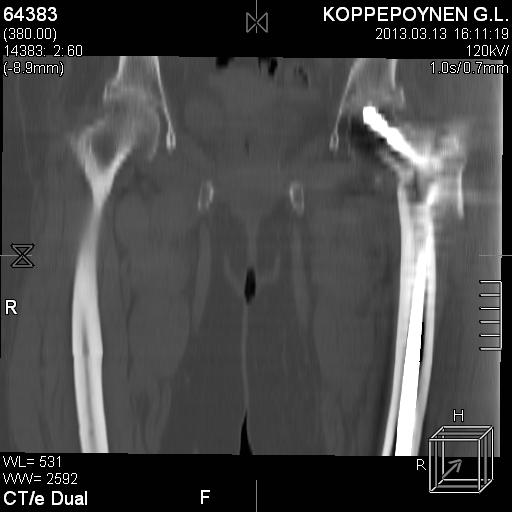

[Ortho] Чрезподвертельный перелом бедра. Остеосинтез стержнем. Перелом металлофиксатора. Дальнейшая тактика?

Делали КТ после операции.